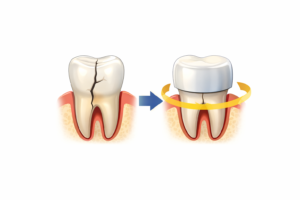

クラック歯に対するクラウン治療の科学的根拠

近年の報告では、

可逆性の歯髄炎(歯の神経の炎症のうち、回復可能なケース)を伴うクラック歯にクラウン(被せ物)による全部被覆(歯を全体をすっぽり覆うこと)を行うことで、約80%のケースで根管治療を回避できた

とされています。

すべてのクラック歯に根菅治療は必要ではありません。

被せものをするだけで歯を守ることができるということです。